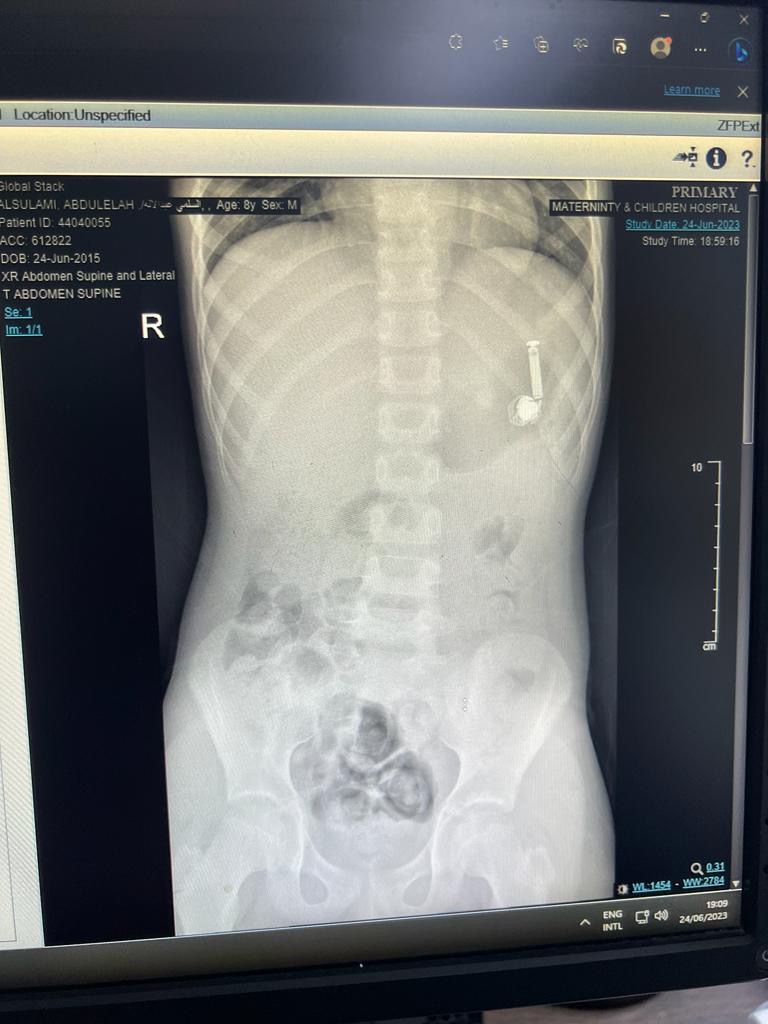

تمكن بفضل الله تعالى فريق طبي بمستشفى الولادة والأطفال عضو تجمع مكة المكرمة الصحي من إخراج سماعة جوال من داخل جوف طفل يبلغ من العمر ١٠ سنوات حيث حضر الطفل مع أهله إلى الطوارىء بعد ابتلاعه للسماعة

في التفاصيل وصلت الحالة لقسم الطوارئ بالمستشفى حيث أخبر الأهل الطاقم الطبي أن ابنهم ابتلع السماعة وعلى الفور تم مناظرة الحالة وعمل الفحوصات الطبية اللازمة وشُكل فريق طبي من قسم المناظير وقسم التخدير للتعامل مع الحالة وتجهيز الطفل لعمل المنظار دون تدخل جراحي

وتكللت العملية بالنجاح بفضل الله تعالى في وقت قياسي تم على إثرها ازالة السماعة والتأكد من صحة الطفل وقد غادر المستشفى وهو يتمتع بصحة جيدة – ولله الحمد